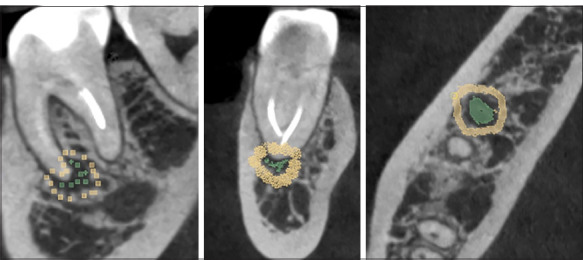

Methods: A retrospective analytical and comparative study was conducted on 100 small field of view (FOV) 50×50 mm CBCT scans collected between the years 2018 and 2023. The study involved qualitative classification of periapical lesions, followed by segmentation and extraction of radiomic parameters. The extracted parameters included first-order features such as energy, entropy, total energy, and uniformity; texture features like grey-level co-occurrence matrix contrast (GLCMC) and neighbouring grey tone difference matrix contrast (NGTDMC); and shape features including elongation, flatness, sphericity, and mesh volume, utilising 3D Slicer and Pyradiomics. The normal distribution of the variables was determined using the Shapiro-Wilk test. Various tests were used to assess significant differences, including Student's t-test, Mann-Whitney U test, ANOVA, and Tukey's post hoc analysis.

Results: Significant differences were observed in the following parameters among the classification levels when classifying periapical lesions according to their volumetric size. There were significant differences in energy with a p-value of 0.001 and total energy with a p-value of 0.02. NGTDMC also showed a significant difference with a p-value of 0.001. A larger volumetric size is associated with greater energy and lower contrast. Significant differences in periapical lesions with erosion were found in shape sphericity (mean 0.34, SD 0.10, p=0.01), energy (mean 3.73×10¹⁰, SD 4.52×10¹⁰, p=0.002), and NGTDMC (mean 0.05, SD 0.02, p=0.001) compared to lesions without erosion. GLCMC was lower in erosive lesions (mean 18.94, SD 6.81, p=0.03) than in non-erosive ones (mean 22.28, SD 8.48). Regular-shaped periapical lesions demonstrated significantly greater elongation (mean 0.794, SD 0.115, p=0.006) and flatness (mean 0.614, SD 0.107, p=0.005) than irregular-shaped lesions. These findings suggest that regular-shaped periapical lesions are more elongated and flatter than irregular ones. No significant differences were found in radiomic features depending on the presence or absence of expansion in the periapical lesion.